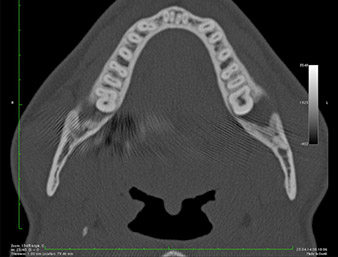

It could be seen in the 3D image (digital volume tomography) that the root remnant was located disto-caudally in the transition from the horizontal to the ascending portion of the mandible (Fig. 2).

DVT-image

Fig. 2: Transverse DVT image of the root remnant in the retromolar region.